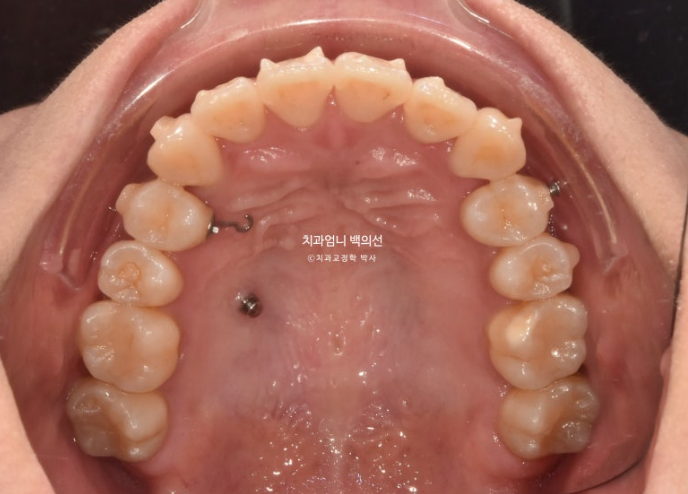

23.09

송곳니가 덧니가 제자리로 들어올 공간이 단 1mm도 없습니다.

심한 덧니입니다.

위도 마찬가지로 사랑니 공간으로 어금니들을 전부 후방이동 시켜 덧니가 배열될 공간을 얻기로 했죠.

첫 세트의 장치는 66개가 나왔습니다.